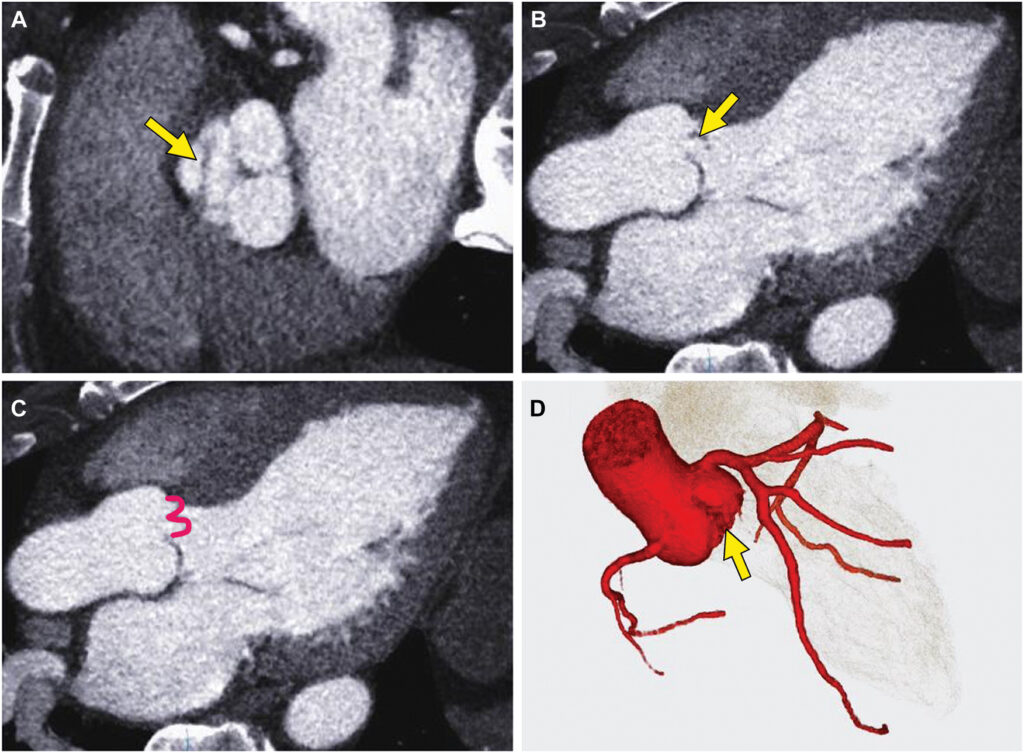

Hemoculturas negativas afastaram a possibilidade de endocardite infecciosa (EI) como etiologia da disfunção valvar e a angiotomografia de artérias coronárias descartou doença arterial coronária obstrutiva, bem como confirmou a dobra transversa no folheto coronariano direito.

O sinal em “W” pode ser observado, ao estudo transesofágico no eixo longo, com a análise em 3D caracterizando a dobra transversa. Este sinal se caracteriza por um formato em W do segmento prolapsado do folheto coronariano direito.